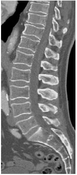

Medical Image Processing is a growing field in medicine and plays an important role in medical decision making. Computer-based segmentation of anatomies in data made by imaging modalities supports clinicians and speeds up their diagnosis making compared to doing it manually. Computed Tomography (CT) is an imaging modality for slice-wise three dimensional reconstruction of the human body in the form of volumetric data which is especially applicable for imaging of bony structures and so for the vertebral column. Most bony structures, such as vertebrae, are characterised by complex shape and texture appearances which turns its segmentation into a difficult task. Model-based segmentation approaches are promising techniques to cope with variations in form and texture of the anatomy of interest. This is done by incorporating information about shape and texture appearance gained from an imaging modality in a model. The model can then be applied to segment the object of interest in target data, however most of the model-based approaches need a model intialisation for a fast and reliable segmentation of the object of interest. This thesis was motivated by novel works on fast anatomical structure localisation with Markov Random Fields (MRFs) and focuses on the sparse structure localisation of single vertebrae in CT scans for a subsequent model initialisation of more sophisticated segmentation algorithms. A MRF based model of appearance, which employs local information in regions around anatomical landmarks and geometrical information through connections between adjacent landmarks, is built on volumetric CT datasets of lumbar vertebrae. The MRF based model is built on a 6 landmark configuration in vertebra volumetric data and is additionally matched with target data. This is done by finding a best fit MRF matching by the Max-sum algorithm among feature points found by a decision tree based feature detection algorithm called probabilistic boosting tree (PBT). Anatomical landmark regions are described by vector spin-images and shape index histograms. Adjacency information is extracted by Delaunay tetrahedralisation where distances and gradient-related angles describe connections between adjacent regions. The results on single lumbar vertebra CT scans show that the MRF approach is applicable on volumetric CT datasets with an accuracy enough for supporting more sophisticated segmentation algorithms such as Active Appearance Models (AAMs).